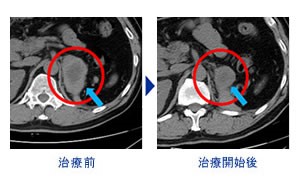

胃癌案例( 油门+刹车 疗法 2疗程 转移部位 消失,缩小)

油门+刹车疗法®接受治疗患者的心声

胃癌转移(53岁 男性)癌症免疫疗法+抗PD-1抗癌剂2疗程

通过朋友的介绍开始了治疗。 肺.淋巴结.肾上腺.有转移.当时进行了1年半的抗癌剂治疗.但是转移部位的肿瘤越来越大.当时的主治医生建议.使用更强的抗癌剂.但是因为有着强烈的副作用所以没有进行.进行的是NK和抗PD-1抗癌剂疗法.2回的治疗.之后CT检查中越来越大的 肺部肿瘤消失.肾上腺.淋巴结也变小了.目前.以中断抗癌剂治疗.没有任何副作用.稳定的状态.

治疗前 治疗进行后